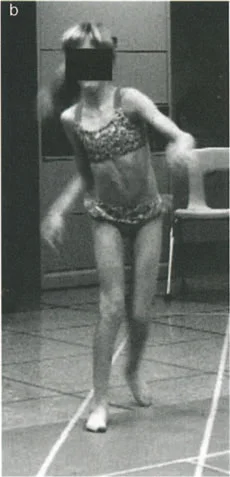

التشوهات الديناميكية هي اختلالات وظيفية تتأثر بموقع المفصل في الفراغ، ووظيفة العضلات، والأهم من ذلك، الطول الفعلي والتوجيه المكاني لأذرع الرافعة الهيكلية أثناء الحركة. على عكس التشوهات الثابتة التي تكون موجودة بغض النظر عن الحركة، فإن التشوهات الديناميكية تظهر بوضوح أو تتفاقم عندما يحاول المريض أداء حركة معينة، مثل المشي أو الوقوف.

من الأمثلة السريرية الكلاسيكية للتشوه الديناميكي هو "حنف القدم الوظيفي" (Functional Equinus)، والذي يُرى غالبًا في حالات الشلل الدماغي أو التشنج بعد الإصابات. في وضع الفحص السريري الثابت، ومع ثني الركبة لإرخاء عضلة الساق (Gastrocnemius)، قد يكون المريض قادرًا تمامًا على ثني القدم ظهريًا بشكل سلبي (Dorsiflexion) لتتجاوز الوضع المحايد. ومع ذلك، أثناء مرحلة الوقوف على ساق واحدة في دورة المشي، تظل القدم في وضع حنف القدم المتيبس.

الأعراض وتأثيرها على الحياة اليومية

- مشاكل في المشي (العرج):

- عرج ترندلنبورغ (Trendelenburg Lurch): في حالات ضعف عضلات الورك المبعدة (مثل الورك الأفحج)، يميل الحوض إلى السقوط على الجانب المقابل أثناء الوقوف على ساق واحدة، مما يؤدي إلى مشية متمايلة.

- المشية القفزية (Vaulting Gait): قد يرفع المريض ساقه السليمة لتعويض قصر في الساق المصابة أو لتجنب حركة مؤلمة.

- مشية حنف القدم (Equinus Gait): حيث تبقى القدم في وضع مدبب (Plantaflexion) أثناء المشي، مما يعيق حركة الكعب عن ملامسة الأرض بشكل طبيعي.

- ملاحظة نمط المشي (Gait Analysis): يراقب الدكتور هطيف بعناية طريقة مشي المريض لتحديد أي أنماط غير طبيعية، مثل العرج، أو المشية المتمايلة، أو عدم القدرة على رفع القدم بشكل صحيح.